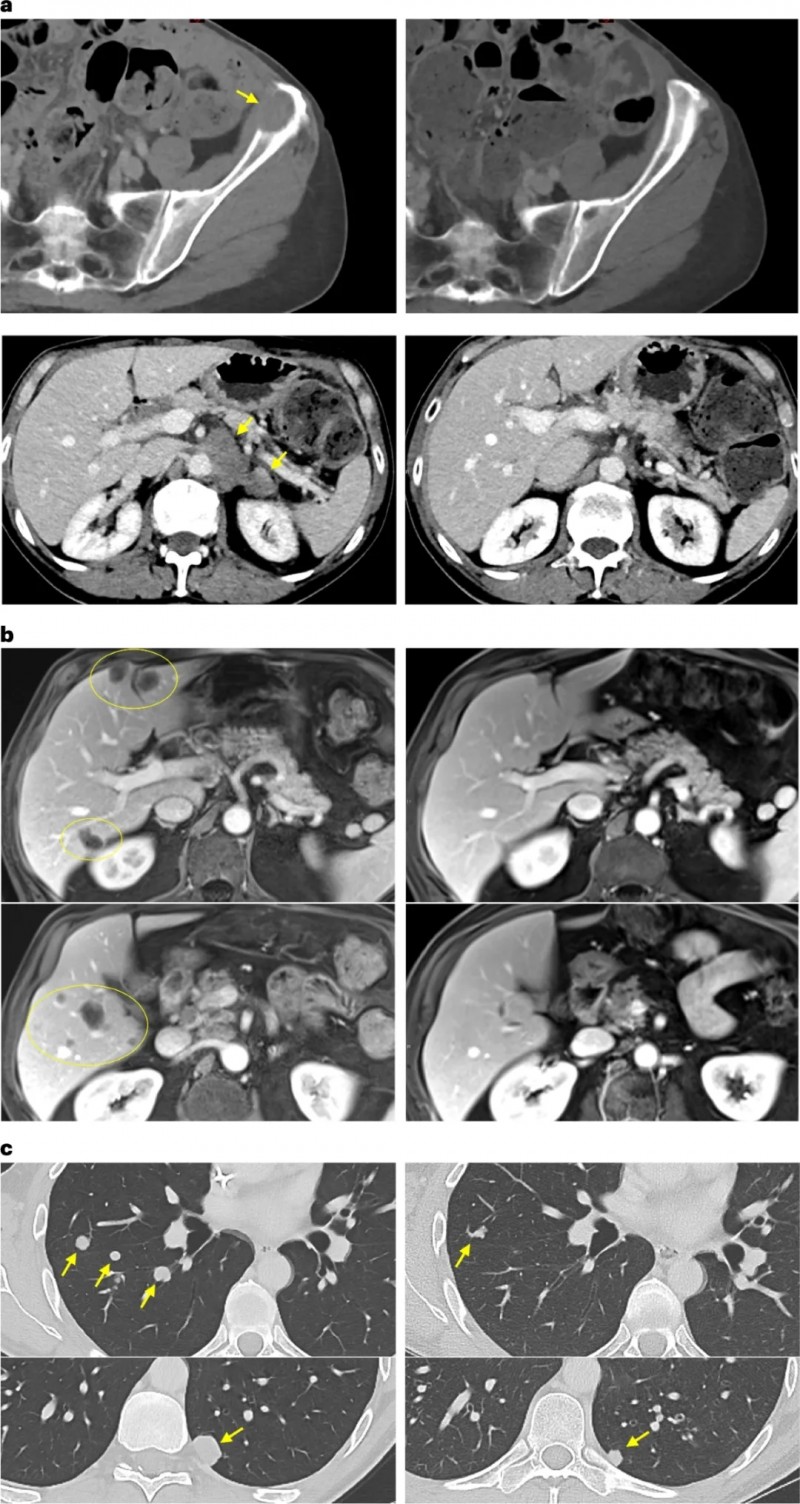

在随访中,有一位患有胰腺癌(被称为癌症之王,致死率极高)且已经转移至肝脏、淋巴结和腹膜的晚期患者。在接受了特定的TIL疗法联合治疗仅仅7个月后,他体内的1个肝转移病灶完全凭空消失,全身整体肿瘤面积大幅缩小了44.1%!

更令人拍案叫绝的是另一位胰腺癌晚期患者,在接受TIL回输后的仅仅6周内,影像学检查震惊了所有的主治医生——他肝脏上密密麻麻的数十个转移瘤,竟然不可思议地全部完全消退!